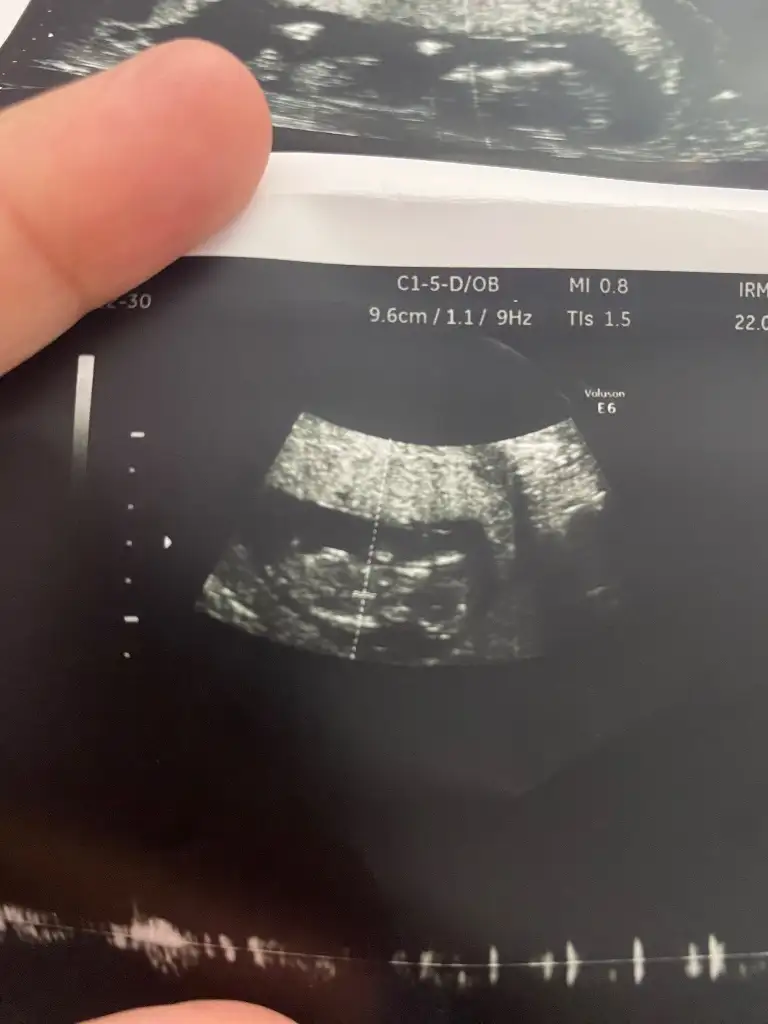

Canım ya banada bak meraktan öleceğim ilk atacağım foto 6 haftalık sonraki 9 ikiside karından